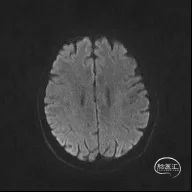

颅脑MR:脑内多发缺血灶、软化灶。